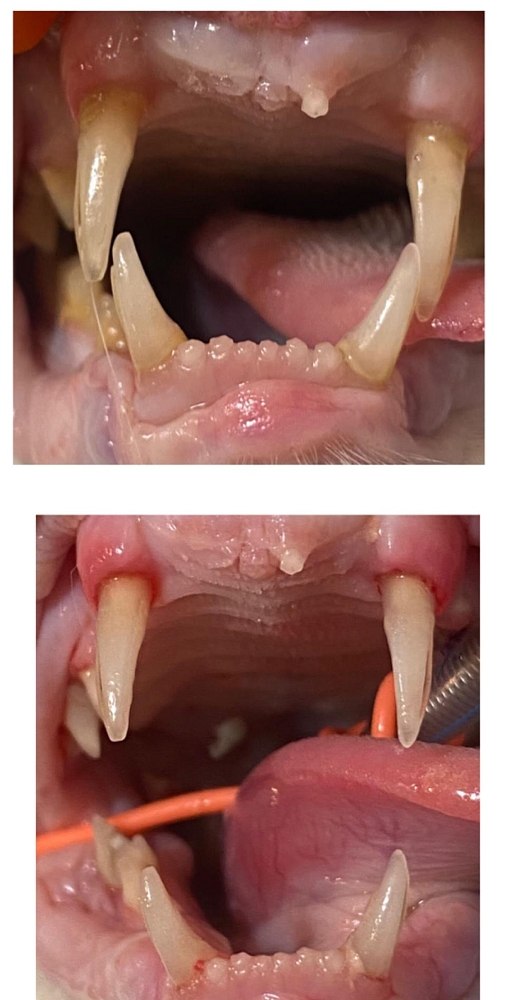

Die grösste Baustelle aber war und ist ihr Gebiss:

Bisher wurde eine Seite behandelt, einige Zähne sind dabei praktisch fast von alleine raus gefallen andere mussten gezogen werden.

Da ihr aufgrund ihres Alters keine zu lange Narkose zugemutet werden sollte, wurde erst eine Seite ihres Gebisses gemacht, die andere Seite folgt in einigen Wochen.

Bereits jetzt speichelt sie weniger und macht allgemein einen besseren Eindruck. Karisma hat vermutlich viele Jahre unter schlimmen Zahnschmerzen gelitten.